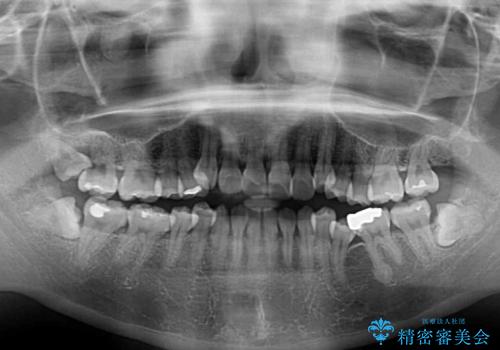

- 前歯がデコボコした上に口元が閉じにくいことを気にして来院された患者様です。

IPR(歯と歯の間を削る)と側方拡大では口の閉じにくさは改善できそうになく、一方で抜歯矯正を行うほどの突出感は認められませんでした。

親知らずを全て抜去し、歯列全体を後方に移動させることで口元の閉じにくさいを改善していくこととしました。

インビザラインでの歯列全体の後方移動は時間がかかりますが、しっかりと装着時間を守っていただいたので、スッキリとした口元に仕上げることができました。